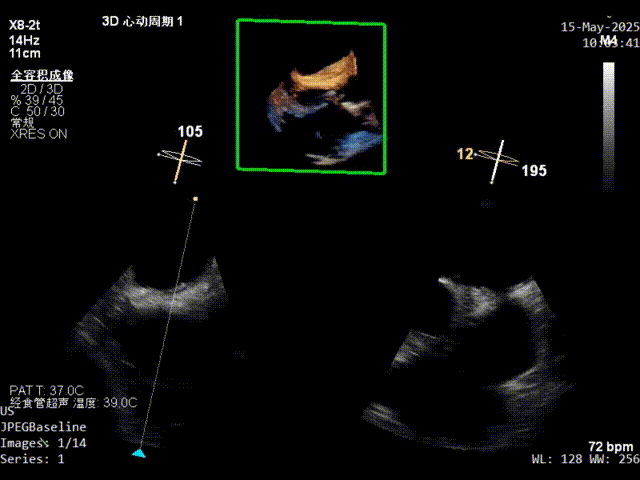

3、模拟穿刺:模拟缝合穿刺点,继发隔与原发隔可基本重合,无错位撕裂风险。

xPlane影像下观察继发隔缝合器捕获情况,待确定为最佳位置后操作手柄对继发隔组织进行穿刺缝合。